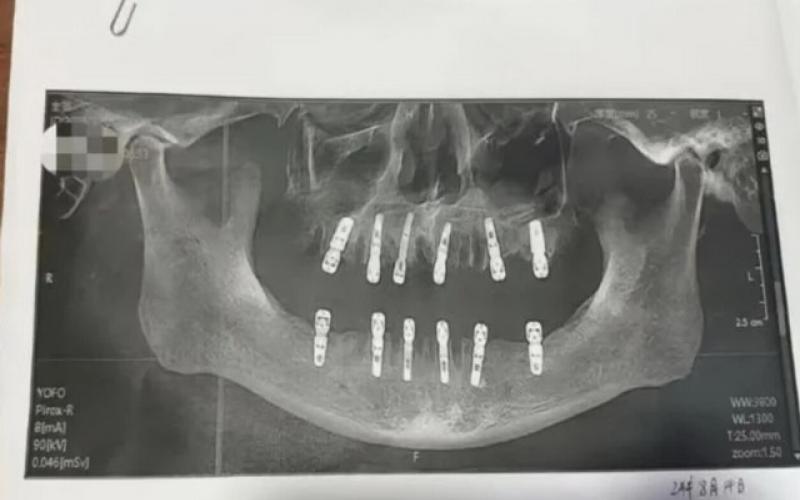

مسئولان چینی در حال بررسی مرگ مرد مسنی هستند که ۱۳ روز بعد از اینکه در یک جلسه درمانی ۲۳ دندان کشید و ۱۲ دندان کاشت فوت کرد.

به گزارش سیتنا، خانم شو (shu)، ساکن شهر یونگ‌کانگ از استان ژجیانگ چین، پس از مرگ پدرش در اثر سکته قلبی، از کلینیک دندانپزشکی محل‌شان شکایت کرد. این زن شواهدی مبنی بر اینکه در یک روز ۲۳ دندان پدرش کشیده و ۱۲ دندان برای او کاشته شده بود به دادگاه ارائه داد و مدعی بود که عوارض درمان دندان‌های پدرش در این کلینیک، ۱۳ روز بعد موجب مرگ ناگهانی او شده است. خانم شو می‌گوید، پدرش تمام ۱۳ روز پیش از مرگش دردهای طاقت‌فرسا داشته است.

بنابر بررسی‌ها، پدر خانم شو،‌ با رضایت کتبی خود اجازه داد تا این درمان سنگین در یک روز انجام شود و یکی از دندانپزشک‌ها که در درمان ریشه دندان، کشیدن دندان عقل نهفته و پروتز کامل تخصص کافی داشت تمام کارهای درمانی دندان پدر خانم شو را انجام داده بود.